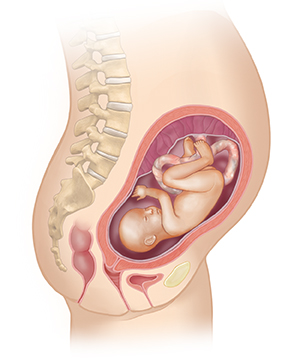

Month 6

Your baby’s fingerprints have formed. Your baby weighs about 1 to 2 pounds (0.45 to 0.91 kg) and is about 12 inches long.